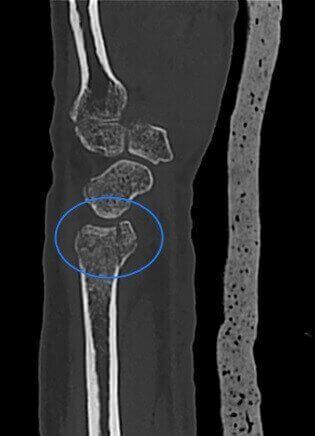

Fractura de la cabeza del radio en paciente con yeso.